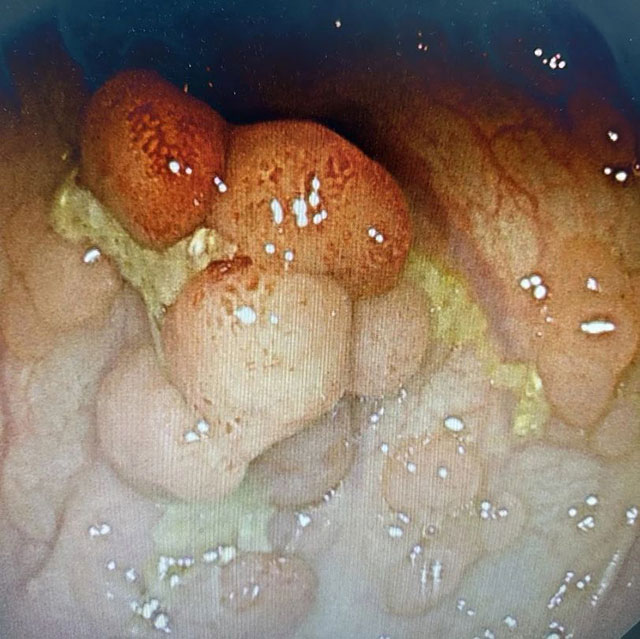

入院后,医生为赵大叔安排了肠镜检查,果真查出了大问题:整个肠壁都是密密麻麻的小息肉,了解了赵大叔的家族史后,医生根据其情况,最终明确诊断为家族性腺瘤性息肉病。最终,医生为其实施了全结肠切除+回肠直肠吻合术。

据肛肠科副主任贾英田介绍,家族性腺瘤性息肉病是一组以结直肠多发腺瘤为特征的常染色体显性遗传的综合征,该病的特征是结肠和直肠内生腺瘤可达数十枚至数千枚,并伴有结肠外表现,常表现为一组疾病群。如果不及时治疗,不可避免地会出现癌变,且可表现为同时多原发性肠癌,属于遗传性大肠癌的一种。

患者的结直肠一般在10~15岁开始出现腺瘤,到25岁时约90%已有腺瘤发生,通常从息肉出现到癌变的平均时间为15年。家族性腺瘤性息肉病平均癌变年龄在39岁(34~43岁),平均死亡年龄40岁。

家族性腺瘤性息肉病的主要症状包括腹痛、腹泻或便频或大便性状改变、便血、贫血、消瘦、发力等。每个患者,甚至在同一个家庭里的患者的临床表现可能不尽相同。至目前为止,手术是治疗家族性腺瘤性息肉病及其癌变的首选方案。